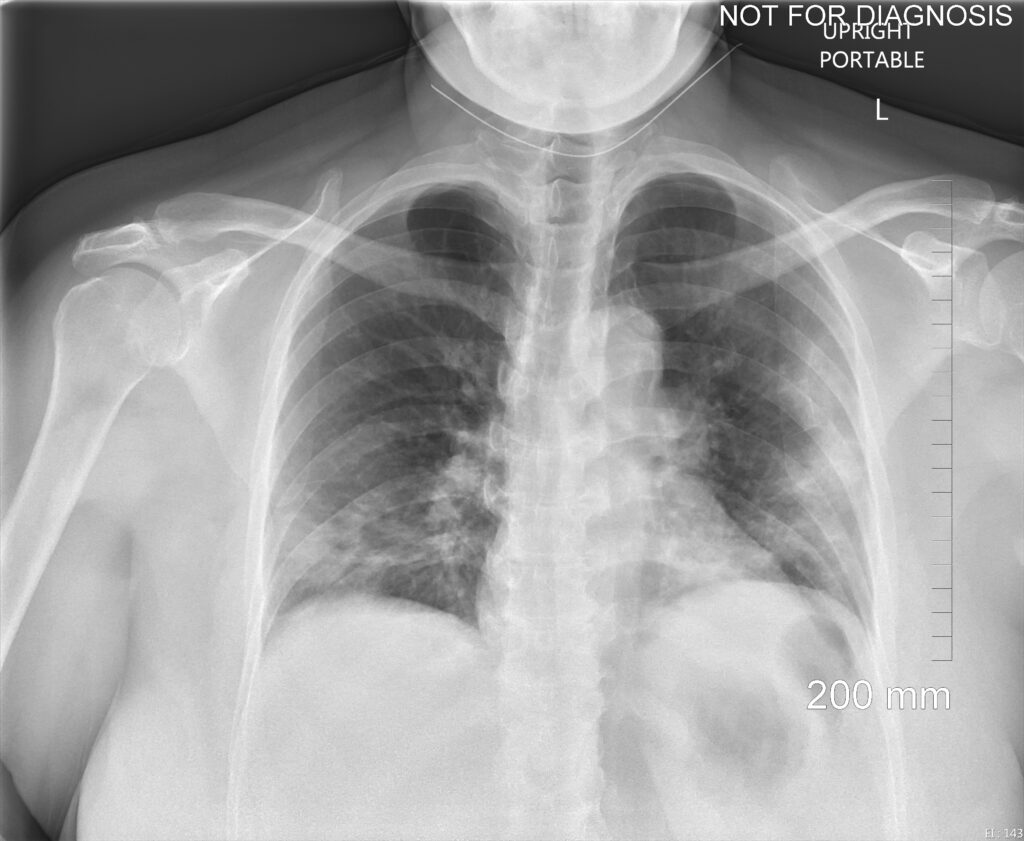

Moderately/severely symptomatic patients: CXR is often negative early, only to turn positive subsequently. The most characteristic findings are basilar and peripheral ground-glass opacities (GGOs) (Fig. 1).

Unfortunately, only a minority of patients have this typical COVID-19 pattern. In most patients, the disease is located more diffusely or elsewhere. Consolidation may be present initially with more severe illness or duration (Fig. 2).

Adenopathy, cavitation, and effusion are uncommon early on. Compared to other viral pneumonias, peripheral lower-lobe GGOs are more common in COVID-19, whereas other pneumonias tend to have more diffuse disease. There is considerable overlap, however.

Follow-up of established disease: On CXR and CT, GGOs and focal area of consolidation often progress and may evolve into a bilateral acute respiratory distress syndrome-like pattern when cytokine storm develops. Less common CT findings include dilated peripheral pulmonary vessels, adenopathy, rounded infiltrates, and signs of bronchial inflammation. Hospital-acquired bacterial pneumonia may complicate COVID-19 and vice versa. Preexisting lung disease (e.g., chronic obstructive pulmonary disease, interstitial lung disease, etc.) further complicate interpretation. Clearing usually starts after 2 weeks.